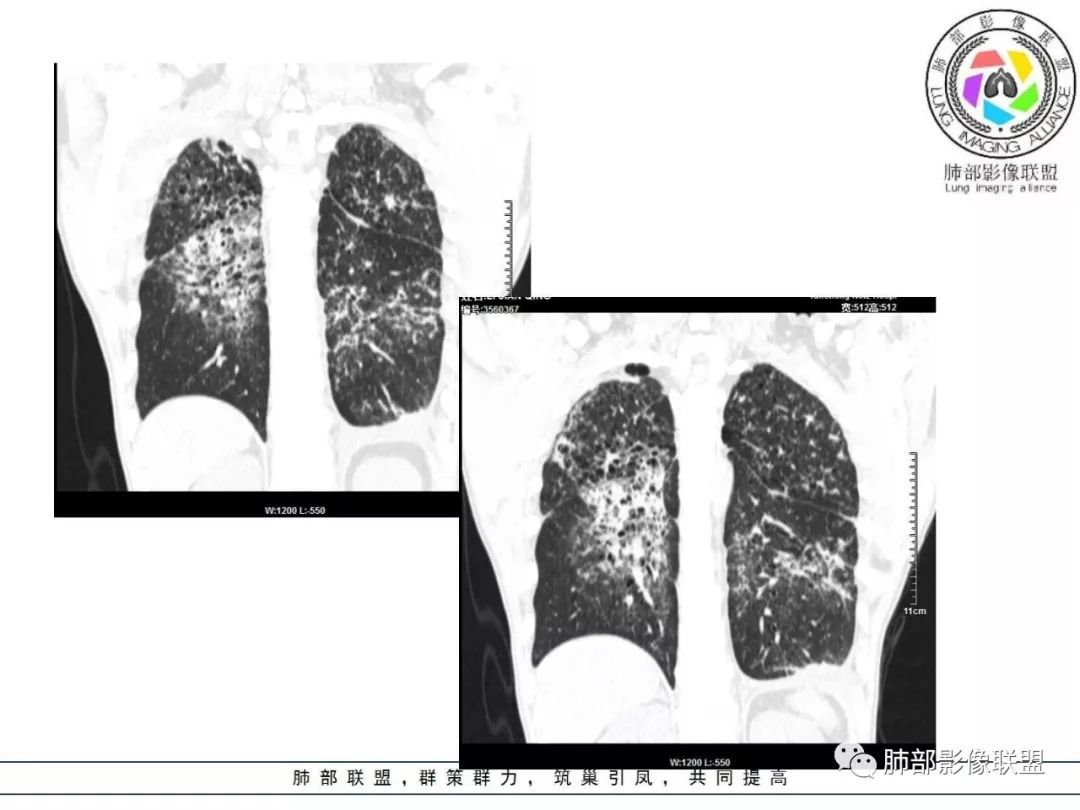

胸部CT:两肺弥漫病灶,磨玻璃影,少许实变,部分累及胸膜,磨玻璃区可见囊?少许胸腔积液,两肺可见结节,支气管血管束增粗,小叶间隔增厚,支气管走形有扭曲扩张,可见纤维化。气肿、大泡。考虑:感染性病变,PCP?查下HIV,CD4,G等。鉴别结核、结缔组织病肺浸润。

中年男性,亚急性起病,发热,咳嗽,黄痰,具体治疗不详,CRP增高,余感染指标及特异性指标不详,基础疾病不详,胸部CT提示双肺散在索条影,右肺为重,胸膜下及中央间质分布为主,磨玻璃影,牵拉性支扩,实变,有囊,LIP合并感染。

胸部CT:两肺弥漫病灶,中央间质分布为主,部分位于胸膜及叶间裂旁,磨玻璃影,斑片影,部分实性结节,肺气囊,支气管血管束增粗,小叶间隔增厚,叶间裂不均匀增厚,支气管走形有扭曲扩张,可见纤维化、气肿、大泡。考虑:LIP加MALT。鉴别PLCH、PCP、结核、结缔组织病肺浸润。

双肺弥漫性病变,多发磨玻璃密度及小叶间隔增厚,大部分沿支气管血管束分布,伴支气管轻度扩张,以午后及晚上发热为主,考虑感染性病变,间质性结核可能大,另双肺多发肺气囊,LIP待排

两肺弥漫病灶,中央间质分布为主,部分位于胸膜及叶间裂旁,磨玻璃影,斑片影,部分实性结节,肺气囊,支气管血管束增粗,小叶间隔增厚,叶间裂不均匀增厚。考虑:间质性肺病,LIP,鉴别OP

病灶呈片状磨玻璃密度影,呈典型的烟花征。磨玻璃影密度偏高,有网结节样改变,与正常肺实质分界清楚,且常见相对高密度的勾画。

病变一般沿血管支气管束分布或小叶分布,一般上肺多于下肺(这与常见继发性肺结核分布相若)。

2. 肺气肿背景(小叶中心性肺气肿);双肺多发病灶整体沿血管支气管束及胸膜下分布,以上叶及下叶背段分布为主,有实变及GGO,边界清楚,有树芽,小叶间隔及中央间质增厚,叶间裂见到多发结节,部分支气管不规则牵拉扩张,提示病灶纤维化明显,结合临床病史,考虑病灶为间质性感染,肺门及纵隔内有钙化淋巴结,小叶间隔结节,考虑淋巴道增值性疾病可能,综合常规要怀疑间质性肺结核。